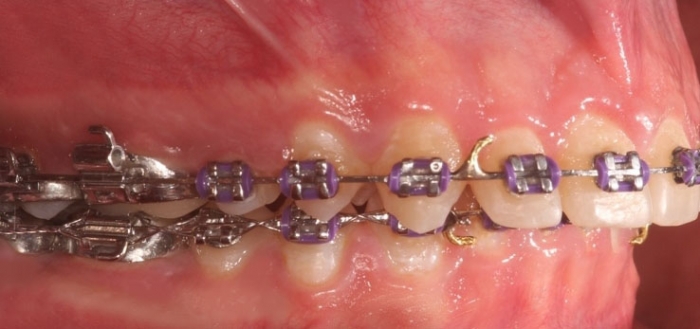

Mordida inicial

Mordida após a cirurgia